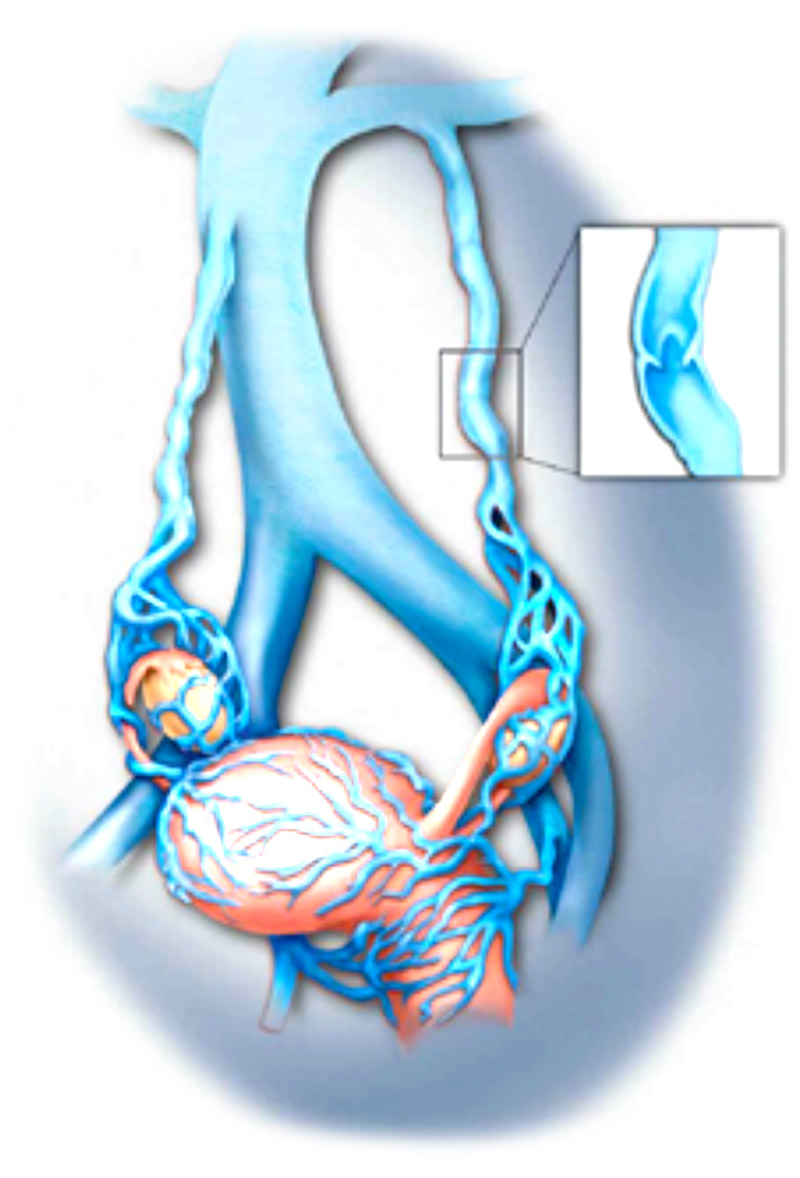

顾名思义,不过是盆底静脉迂曲扩张,由于在深处,只有少部分患者会有会阴、臀部及大腿静脉曲张的外在表现,单纯静脉曲张还好,对生活质量影响小,如果曲张严重就会产生一系列的临床表现,尤其是慢性的腹部不适,医学上有术语叫做盆腔瘀血综合征。

盆腔淤血综合征其实是盆腔曲张基础上出现,而盆腔的静脉丛特别丰富,曲张最为多发的是左侧的卵巢静脉。左侧容易出现曲张的原因主要是因为人体特殊的解剖构造所决定的,而女性更为高发则是因为怀孕过程增加了本病的发生机会。男性当然也有,只是比较少见,主要表现出精索静脉曲张。